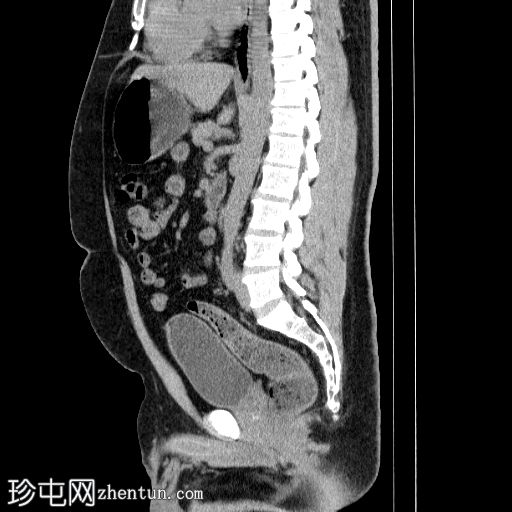

3.jpg

矢状位

平扫

左侧肾盂输尿管连接部(PUJ)可见一枚较大的不透射线结石,最大直径达24 mm,平均CT值约为1160 HU。该结石引起反压改变,导致明显的左肾积水。

此外,左肾中极肾盏内可见一枚直径约13 mm的非梗阻性不透射线结石,平均CT值为1100 HU。

另外,左肾下极肾盏内可见多枚聚集性不透射线结石,总直径约20 mm,平均CT值约为1140 HU。

偶然发现的异常包括前列腺内多发粗大钙化灶,主要位于尿道周围,并伴有轻度肝肿大。